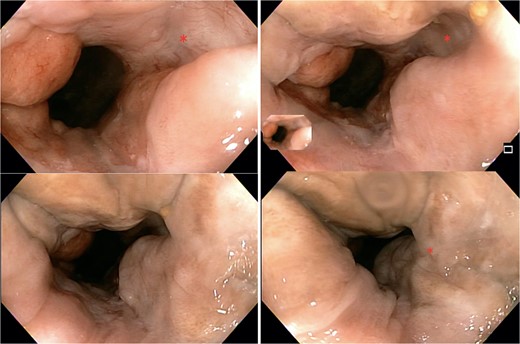

The patient was regularly follow-up a 4-month intervals, and no recurrence was found during a follow-up period of 12 months. Patient remained with good anorectal and sexual function. A 1 year follow-up colonoscopy was performed, finding complete response, with a flat white scar, telangiectasia and absence of both ulcer and nodularity (Fig. 6).

Colonoscopy findings. Image showing a flat white scar, telangiectasia, and absence of both ulcer and nodularity.